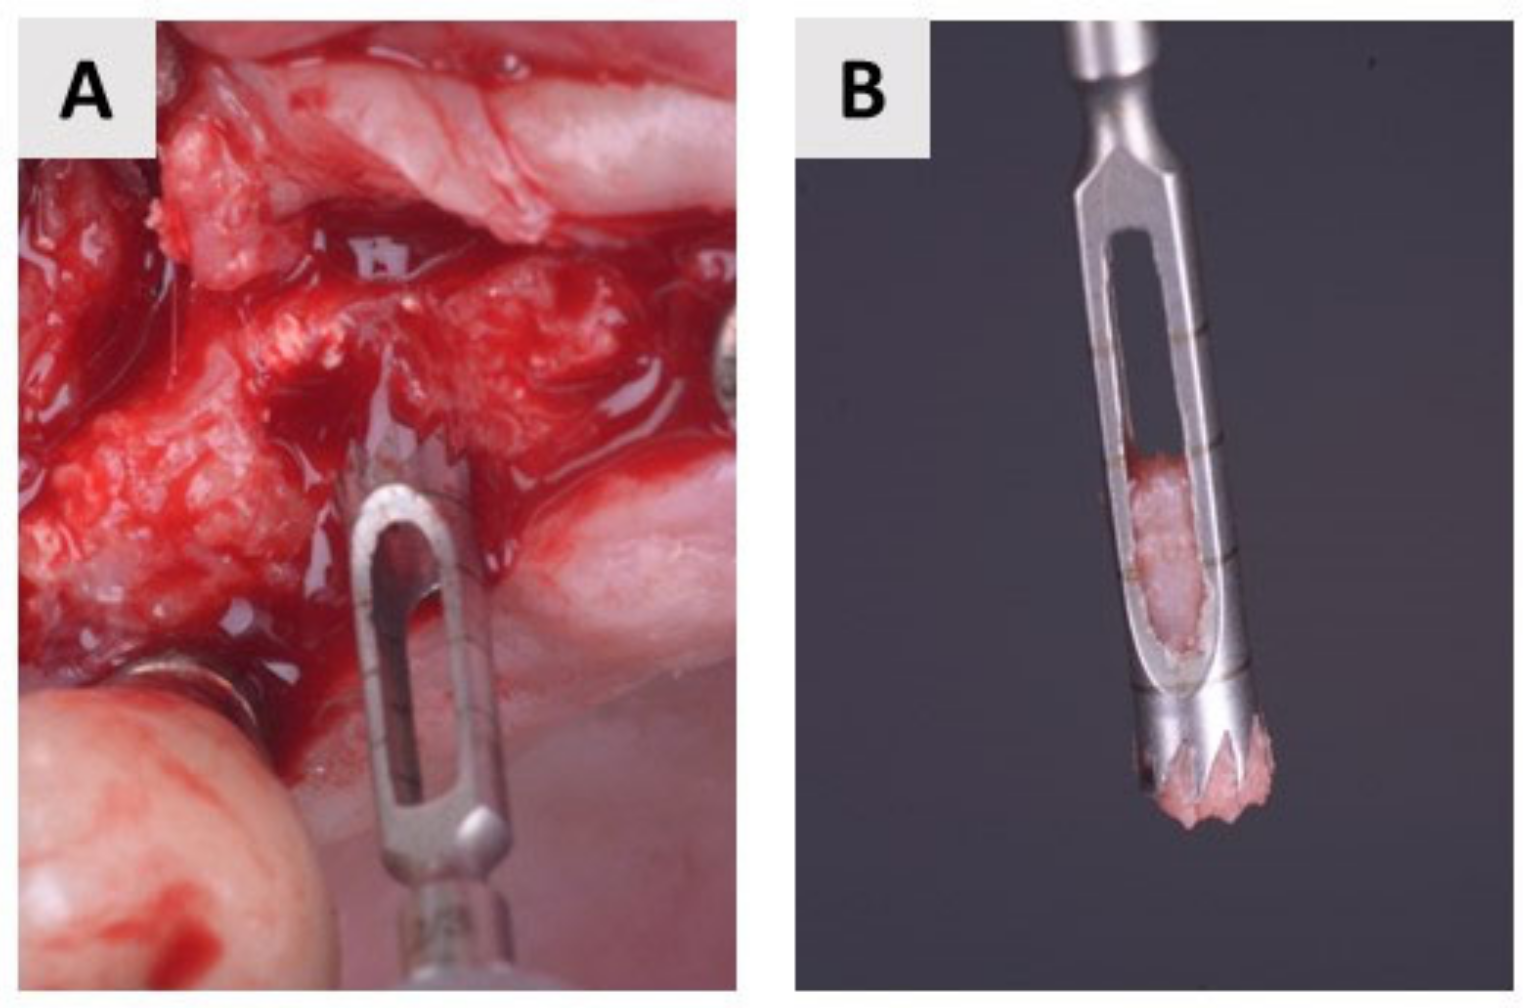

4.3. Bone Biopsy Collection